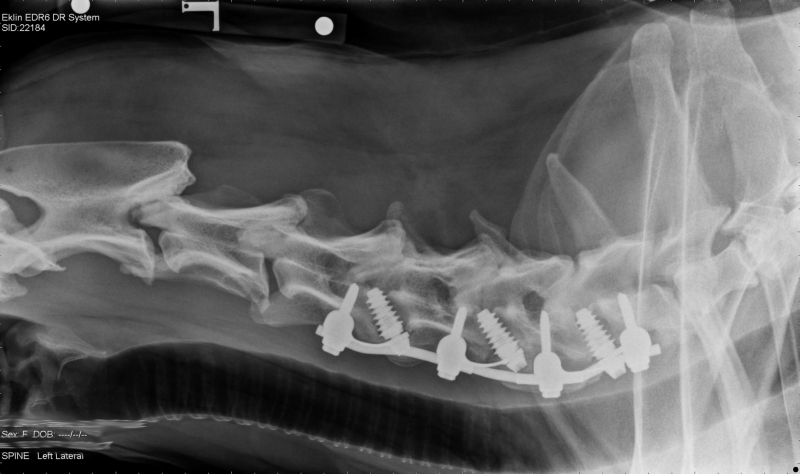

After a long and heart-breaking discussion with Ellie’s owners it was decided that the best course of action was surgery to try and alleviate Ellie’s neurological problem. Distraction of the affected bones followed by fusion of all the bones was carried at all three sites by placing an inter-vertebral distraction screw (FITS, Fitz inter-vertebral Traction Screw) between each vertebral body to replace the discs and then joining each of the three vertebrae using plates anchored to each vertebral body, linked together with rods and linked to the inter-vertebral screws. Bone harvested from both of Ellie’s shoulder joints and was packed along the ventral surfaces of C4, C5, C6 and C7 to help encourage the bones of the neck to fuse together.

Post-surgery radiograph showing distraction fusion implants at the base of the cervical spine.